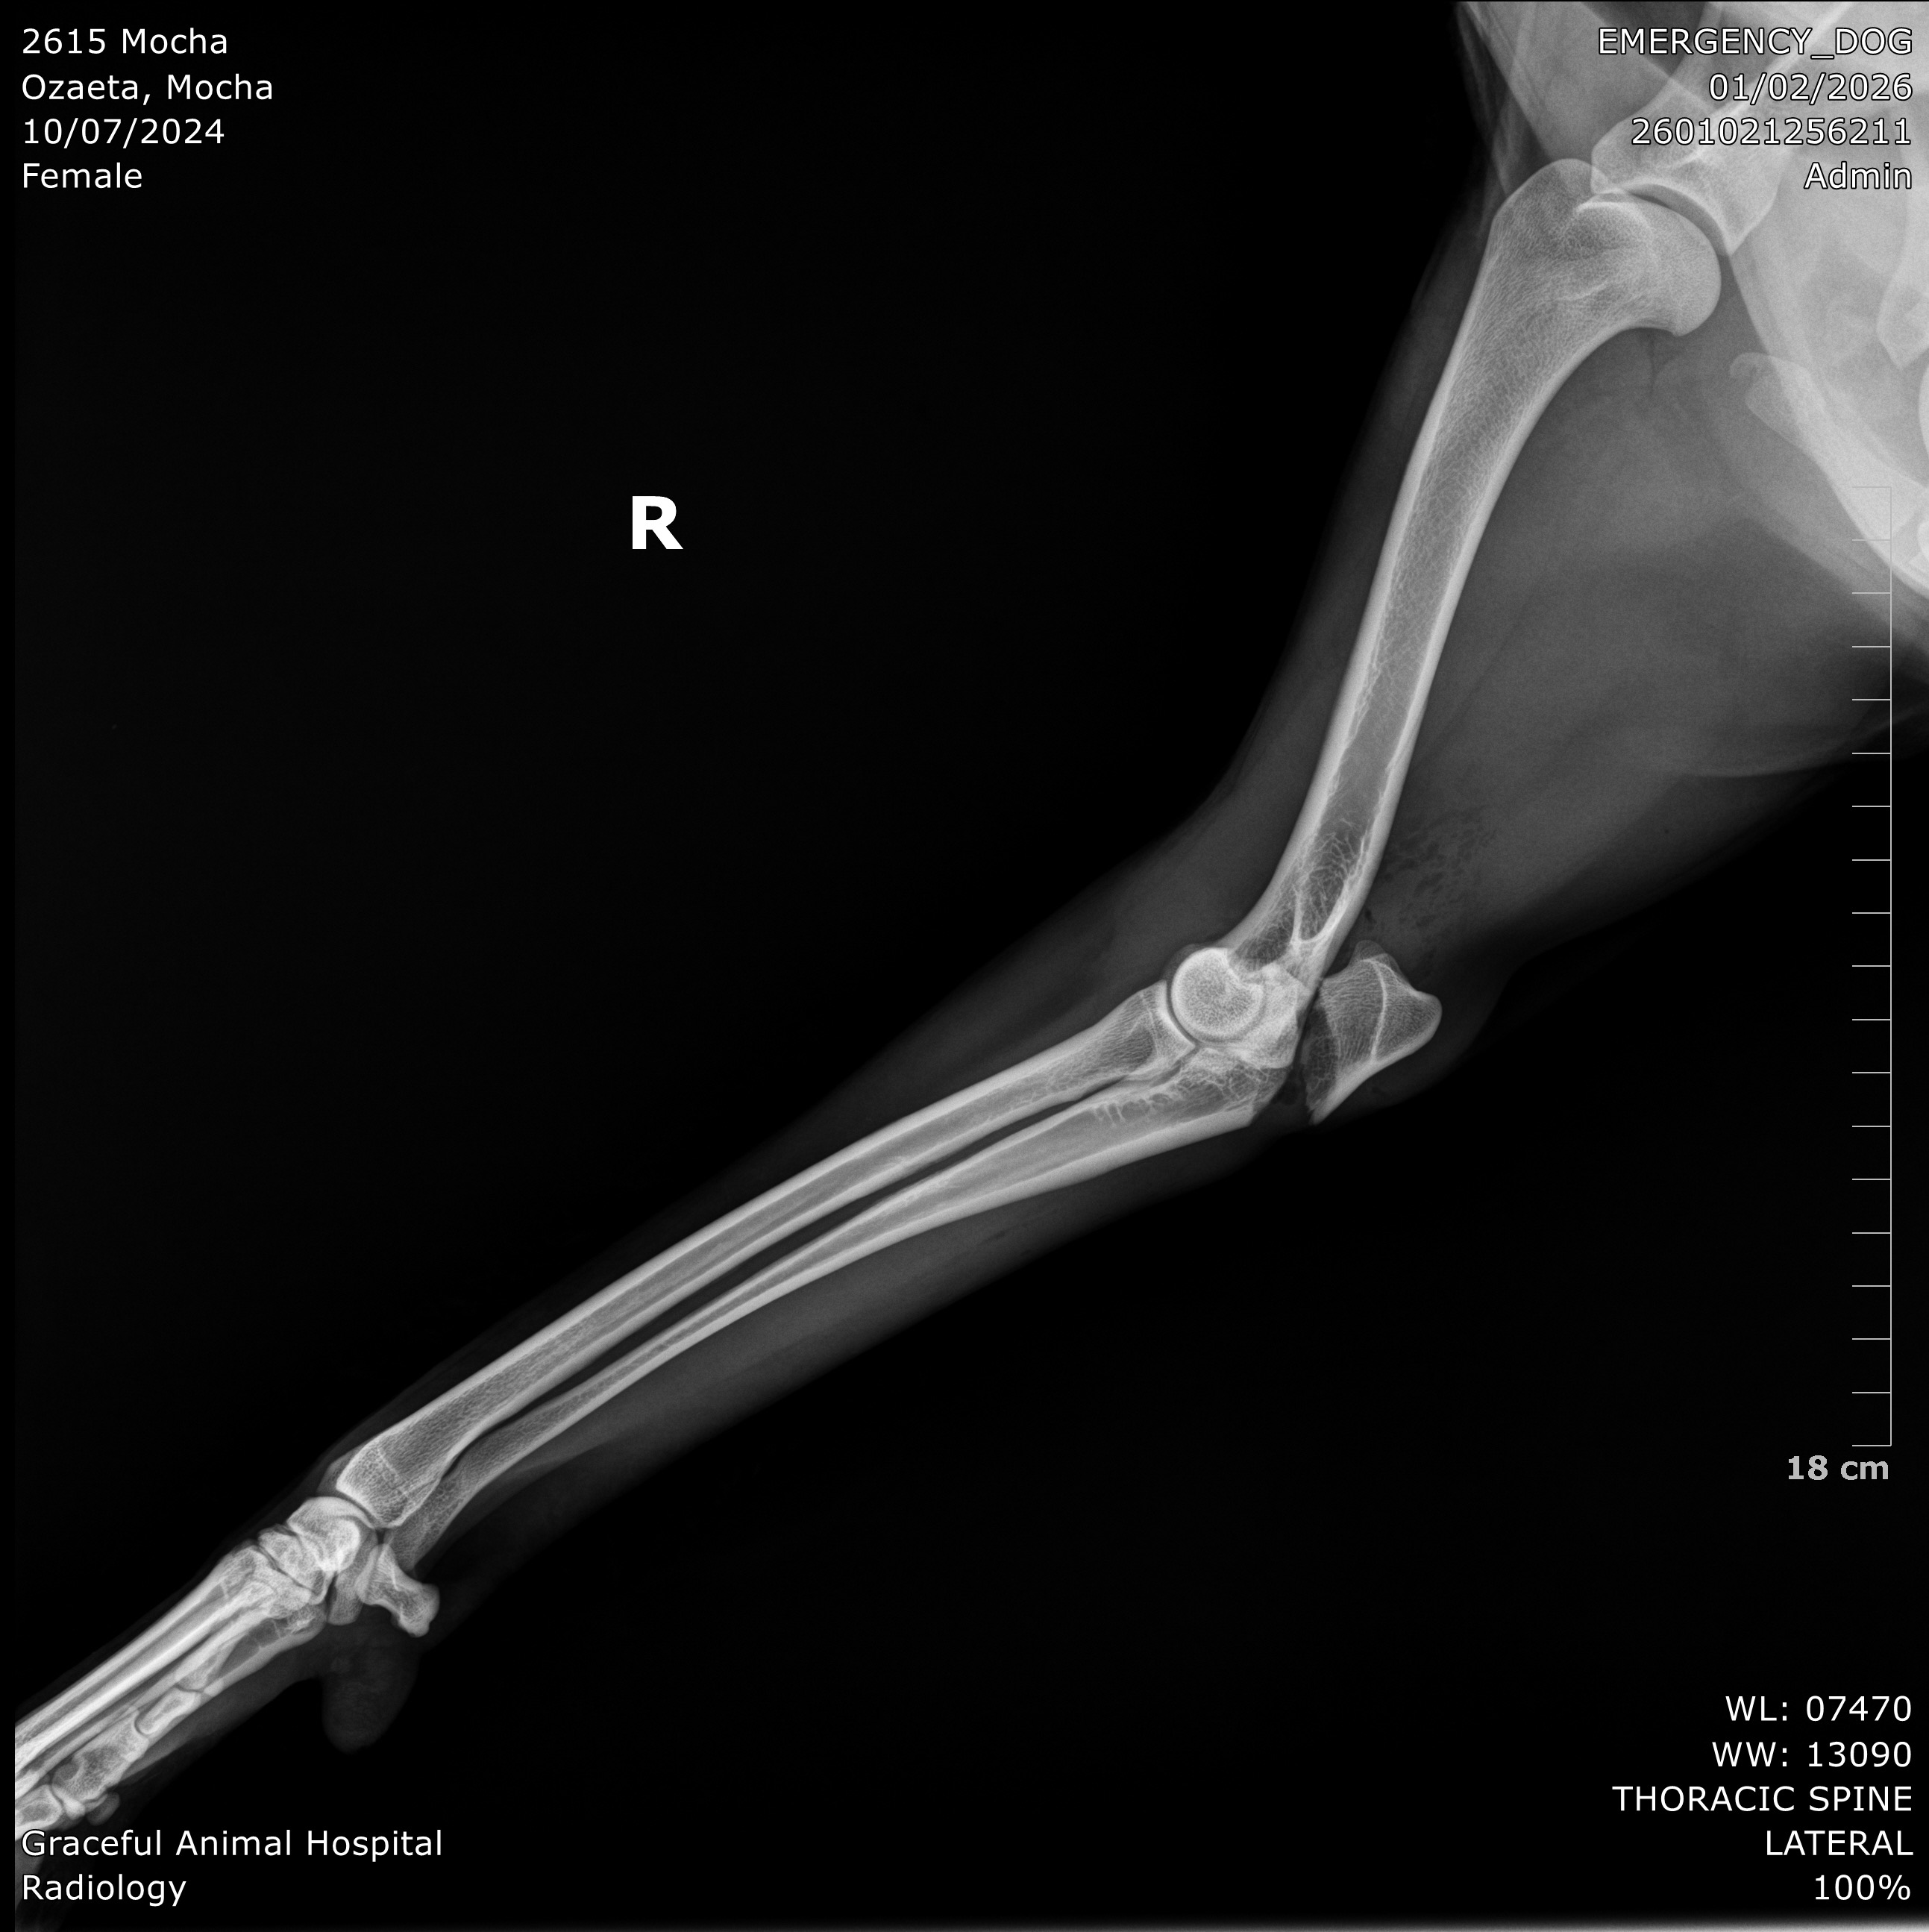

One week ago, Mocha was tragically hit by a careless driver. Since that day, our lives have completely changed. She suffered a broken right front elbow and severe nerve damage to her left front leg, which has left her paralyzed. Mocha is unable to walk and drags herself to move. She also suffered a liver contusion, which we are monitoring closely.

After careful consideration, we made the difficult decision to take Mocha to Tijuana, Mexico, where experienced veterinarians quoted us $3,200 for:

• Elbow repair surgery

• Muscle and nerve injury surgery